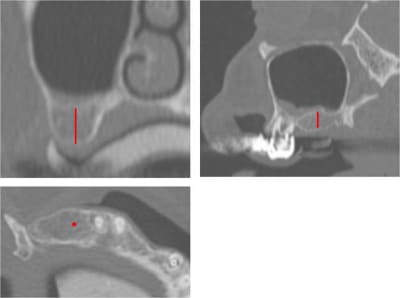

Pose d’un implant au maxillaire dans une zone de faible densité

Léger summers

je connais cette radio!!!!!...;-))

P.S: tout va bien, prothèse d'usage prévue fin septembre...;-))